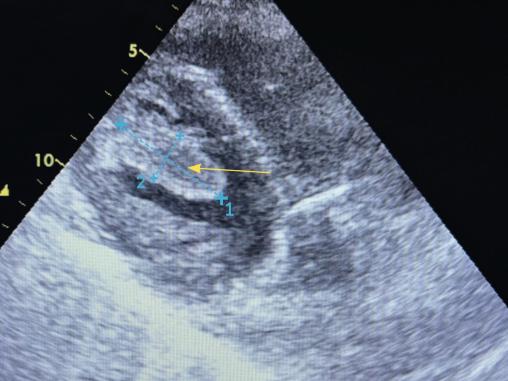

Une échocardiographie transthoracique montre la présence d’un thrombus intraventriculaire gauche (VG) apical (fig. 2), siège d’une akinésie de l’apex et une fonction globale conservée avec fraction d’éjection du VG (FEVG) estimée à 50 %.